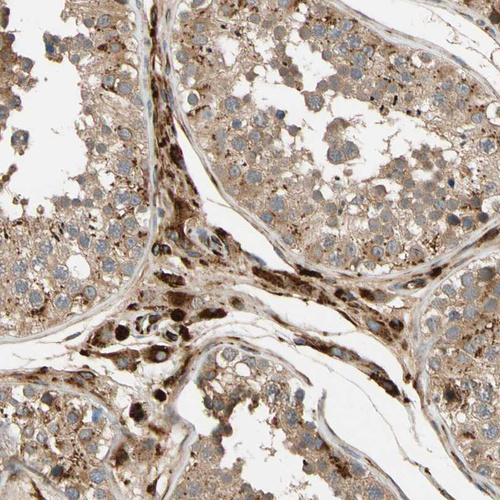

Immunohistochemical staining of human lymph node shows moderate cytoplasmic positivity in germinal center cells.